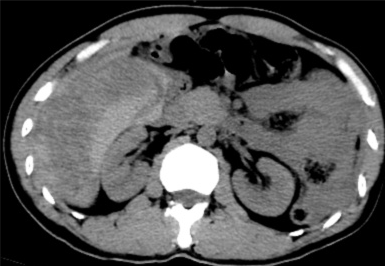

据悉,患者既往有多年乙型肝炎病史,突发右上腹剧烈疼痛入院。患者入院时血压70/40mmHg,心率110次/分,全腹压痛。血常规血红蛋白87g/L,甲胎蛋白>1210 ng/ml。腹部B超检查及CT平扫检查示“肝肿瘤并出血,腹腔积血积液”。

入院后,为患者给予补液,在局部麻醉下行DSA引导下经导管肝肿瘤动脉栓塞术。